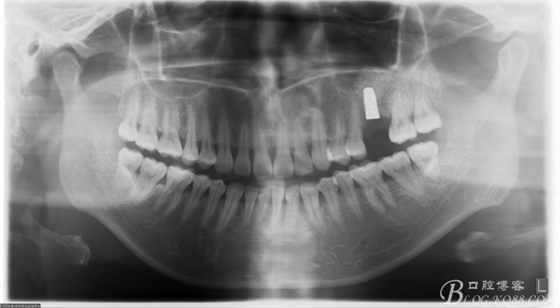

術(shù)后X片。上頜竇外提一例

5個月后X